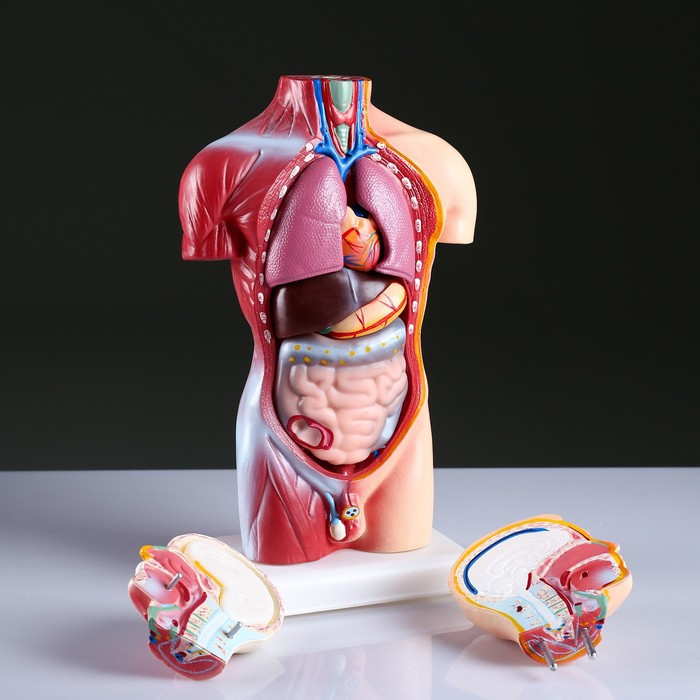

Анатомические модели